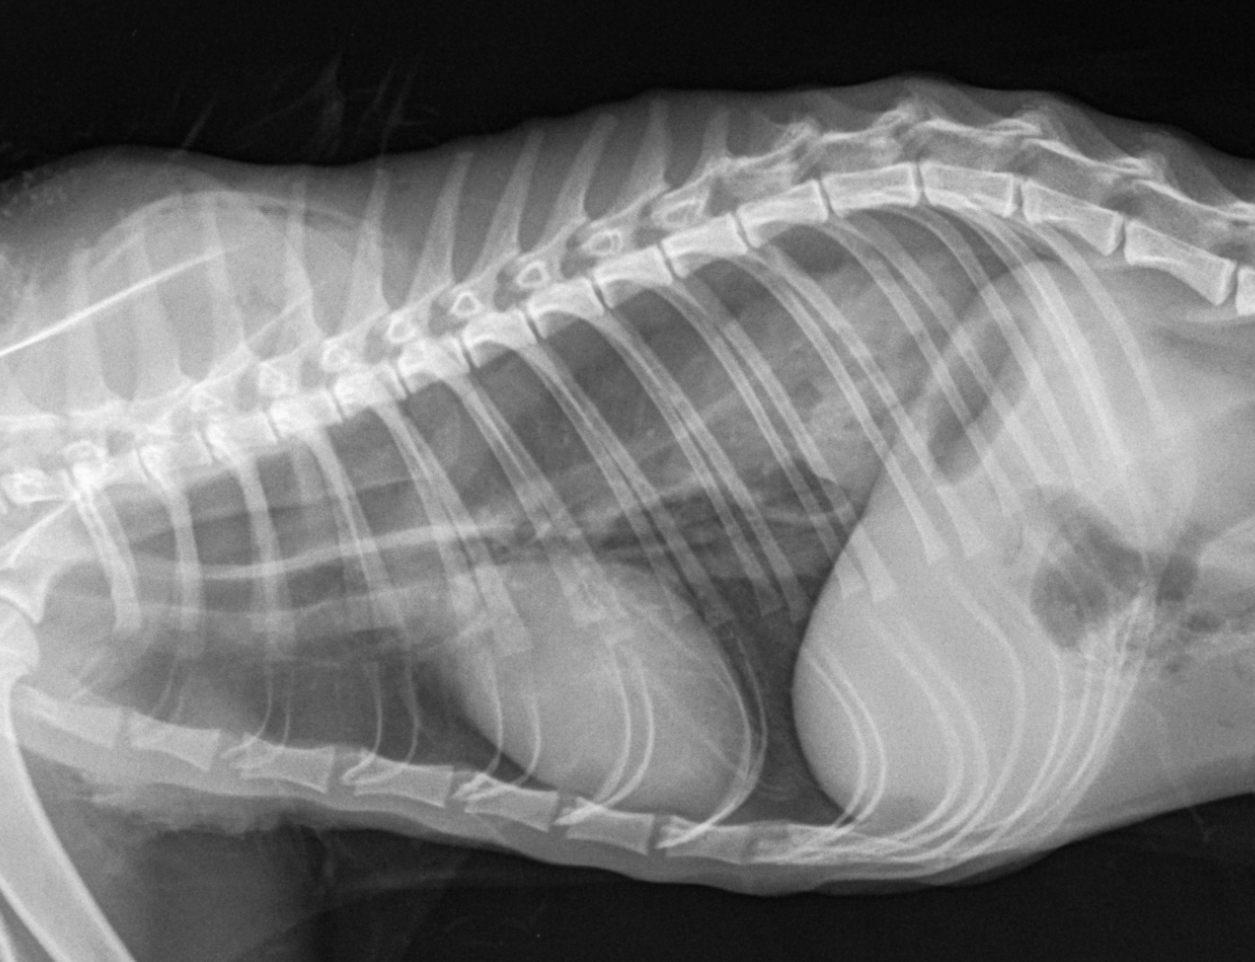

Грыжа У Котят Фото

Грыжа У Котят Фото 110 фотографий